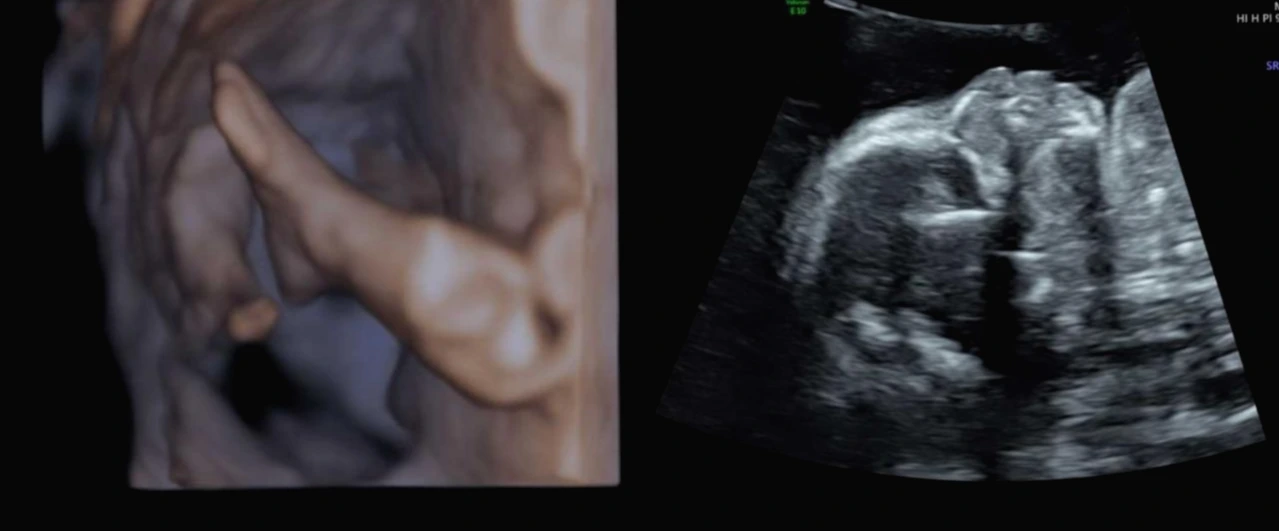

내 나이와 혹시나 있을 불상사를 위해서 첫째 둘째 때 안 했던

비싼 하모니 테스트도 하고

노산에 셋째를 출산하는 저를 위해 순산 기원 부탁드린다.

출산을 이미 두 번 해봤지만 그래도 또 하려니 무섭다.

제발 무통 맞고 아픔 없이 아이가 무사히 나올 수 있기를.